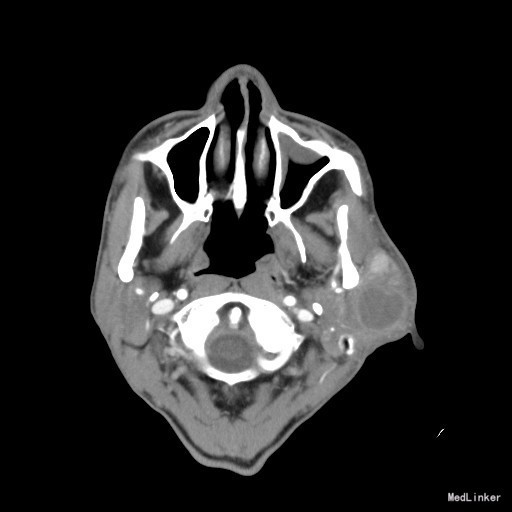

查体:左侧腮腺区肿物,表面皮肤暗黑,大小约5*4cm,边界清,稍有压痛,无伴口角歪斜及闭眼不全,导管口未见异常分泌物。 辅查:CT:双侧腮腺内多发病变,考虑良性病变,腺淋巴瘤与混合瘤鉴别,前者可能性大。

随访:术后病理结果示:符合腺淋巴瘤。 讨论:腮腺肿瘤中良性肿瘤多见,约占75%。腺淋巴瘤又称Warthin瘤,占5~10%,常见于50岁以上高龄男性,通常为多发或双侧发病,多位于腮腺浅叶下极,常表现为发展缓慢、表面光滑,质地较软的无痛性肿块,CT上多表现为分叶和多发小囊样表现,MR上因易形成蛋白含量高的囊腔,T1WI,T2WI均呈高信号,颇具特征性。